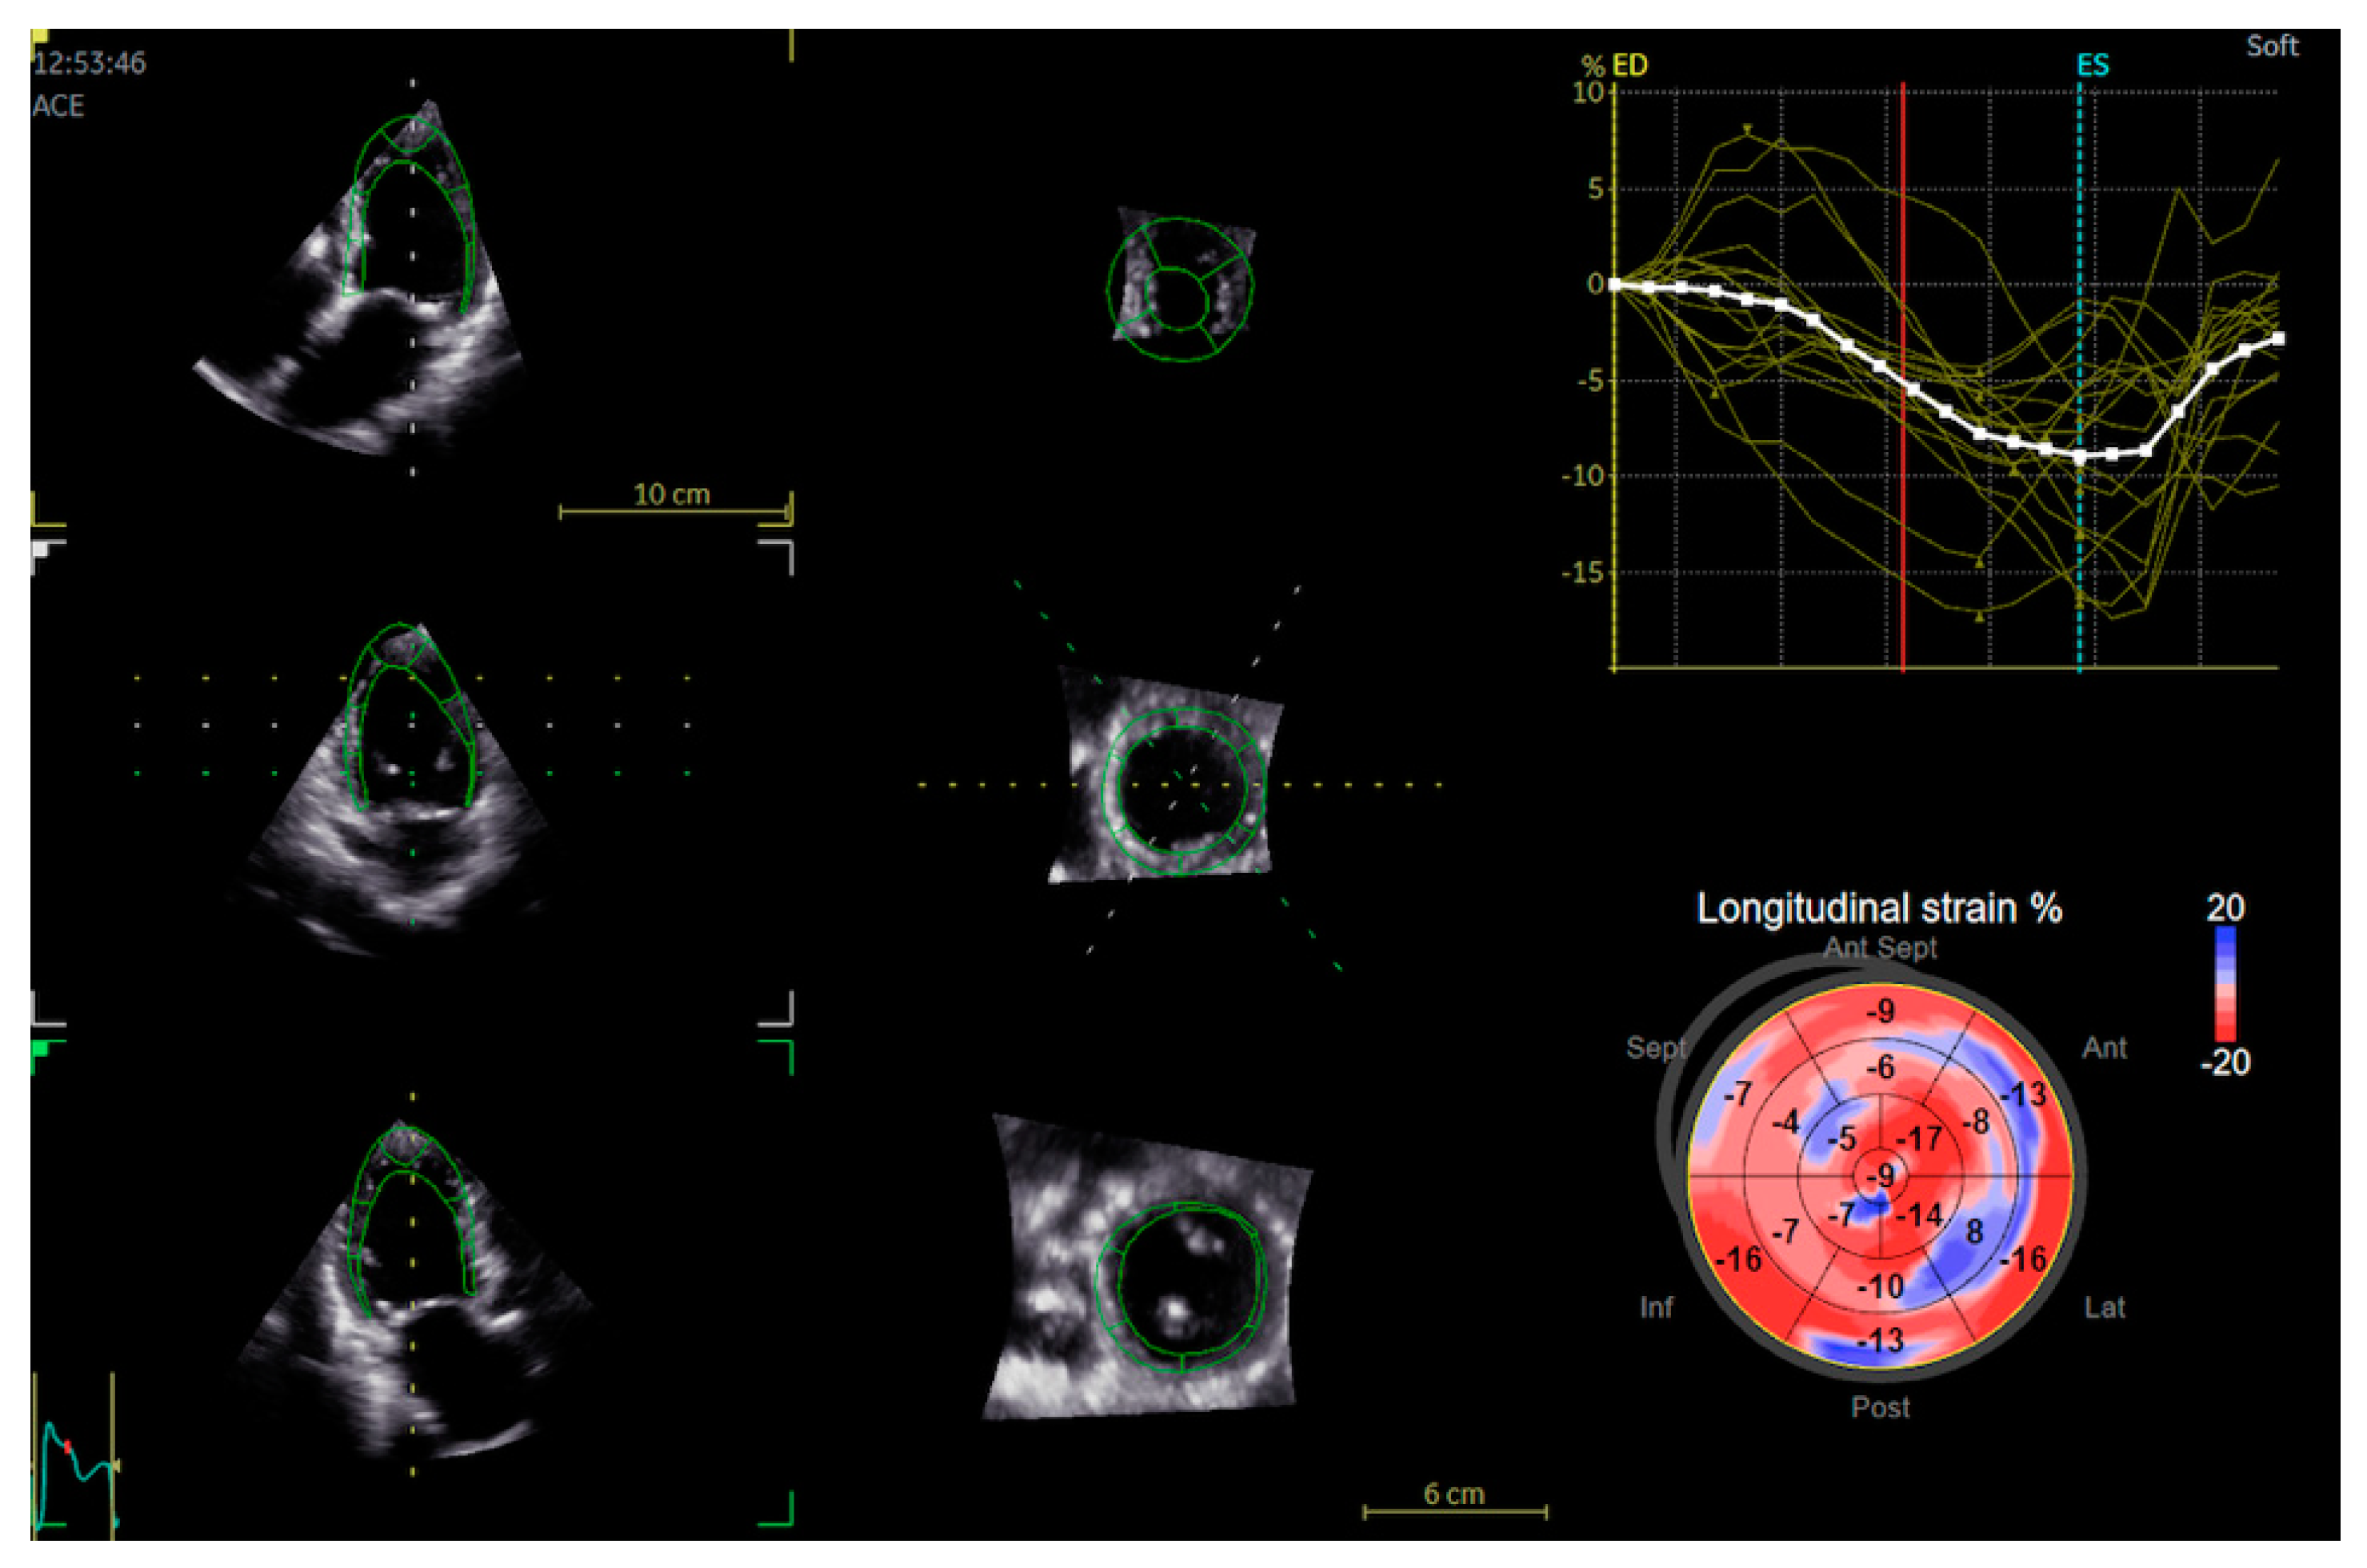

The Agreement of a Two- and a Three-Dimensional Speckle-Tracking Global Longitudinal Strain

2. Materials and Methods

2.2. Echocardiography